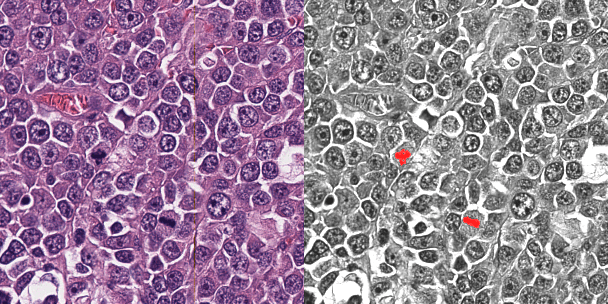

Abstract:Background: Histopathology is an important modality for the diagnosis and management of many diseases in modern healthcare, and plays a critical role in cancer care. Pathology samples can be large and require multi-site sampling, leading to upwards of 20 slides for a single tumor, and the human-expert tasks of site selection and and quantitative assessment of mitotic figures are time consuming and subjective. Automating these tasks in the setting of a digital pathology service presents significant opportunities to improve workflow efficiency and augment human experts in practice. Approach: Multiple state-of-the-art deep learning techniques for histopathology image classification and mitotic figure detection were used in the development of OncoPetNet. Additionally, model-free approaches were used to increase speed and accuracy. The robust and scalable inference engine leverages Pytorch's performance optimizations as well as specifically developed speed up techniques in inference. Results: The proposed system, demonstrated significantly improved mitotic counting performance for 41 cancer cases across 14 cancer types compared to human expert baselines. In 21.9% of cases use of OncoPetNet led to change in tumor grading compared to human expert evaluation. In deployment, an effective 0.27 min/slide inference was achieved in a high throughput veterinary diagnostic pathology service across 2 centers processing 3,323 digital whole slide images daily. Conclusion: This work represents the first successful automated deployment of deep learning systems for real-time expert-level performance on important histopathology tasks at scale in a high volume clinical practice. The resulting impact outlines important considerations for model development, deployment, clinical decision making, and informs best practices for implementation of deep learning systems in digital histopathology practices.